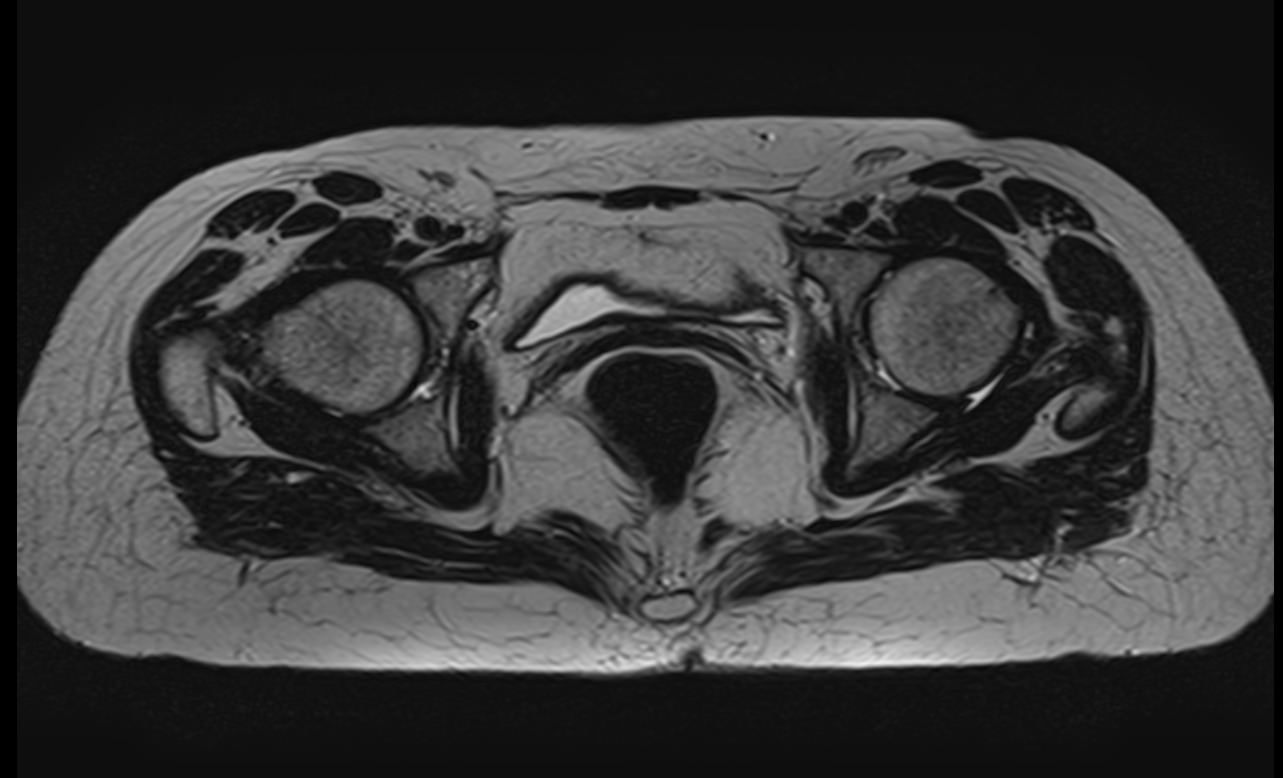

Максимально информативным способом диагностики заболеваний тазобедренных суставов является магнитно-резонансная томография. Кроме высокой информативности МРТ обладает такими преимуществами как достаточная быстрота, безболезненность, неинвазивность и безопасность. Метод основан на использовании действия на ткани внешнего магнитного поля, при этом не применяется вредное рентгеновское излучение. Поэтому МРТ можно проводить столько, сколько необходимо. Например, это бывает важно во время предоперационной подготовки и для динамического наблюдения в ходе лечения, в том числе, в послеоперационном периоде.

В клинике «Доступная медицина» МРТ тазобедренных суставов проводится на новейшем высокопольном томографе экспертного класса TOSHIBA VANTAGE TITAN 1,5 Тесла. Томограф производит сканирование зоны исследования, делая послойные срезы в разных плоскостях с шагом от 1 мм, затем с помощью цифровых приложений преобразует полученные данные в трехмерные изображения превосходного качества. МР томография дает детальную информацию о состоянии костных структур сустава, сухожилий, связочного аппарата, синовиальной оболочки, суставной полости, нервов, сосудов и прилегающих мягких тканей. Это позволяет поставить точный и достоверный диагноз и назначить вовремя лечение.